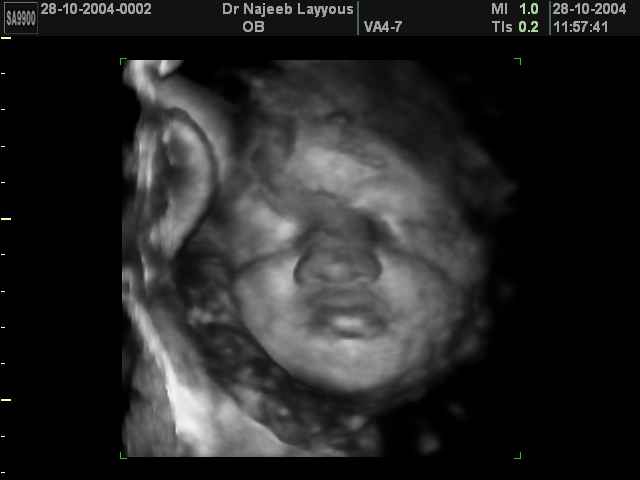

3D Fetal Face Ultrasound Scan Photos